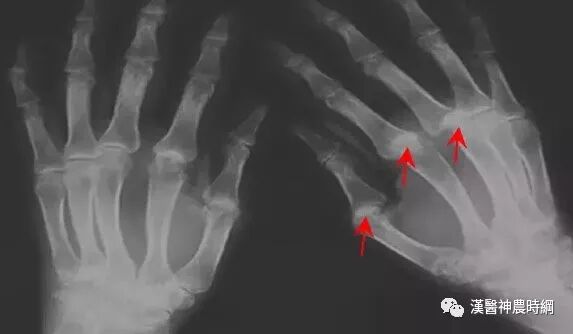

1.可检测到抗核抗体谱、类风湿因子、抗中性粒细胞胞浆抗体、抗磷脂抗体等抗体。 2.影像学检查可发现关节病变。 3.临床上表现为关节肿胀或疼痛、关节活动受限等。

关节异常:在风湿病的病变中,会在患者的关节处最先发生异常,不少的人会以为是关节炎。在平时如果出现莫名其妙的腰腿痛,或是在阴雨天的时候关节疼痛,这就是风湿的典型表现。如果严重时受累关节变成僵硬而畸,膝、肘、手指、腕部都固定在屈位,最后不能动弹。